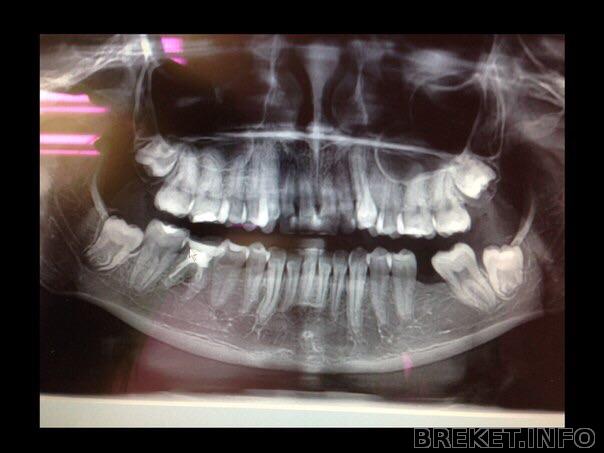

А насчет зубов мудрости, вам перед установкой брекетов должны были сделать панорамный снимок, как на фото (прилагаю). И по слепкам ортодонт должен был рассчитать: надо ли их удалять, или места хватает и они будут расти.

Такой снимок делают около 700 рублей почти в каждой клинике в больших городах.